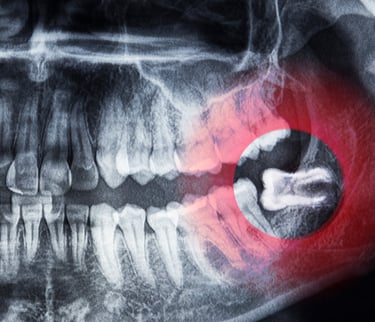

تشخيص ضرس العقل المطمور

تقييم شامل بالأشعة لتحديد درجة الانطمار والمخاطر المحتملة

يتم استخدام الأشعة البانورامية أو CBCT للحصول على صورة واضحة للعصب والعظم.

الخطوة الأولى ضرورية لتحديد ما إذا كان الضرس يحتاج قلعًا جراحيًا أو عاديًا.

• تحديد درجة الانطمار بشكل دقيق باستخدام الأشعة.

• تقييم المسافة بين الضرس والعصب لتقليل المخاطر.